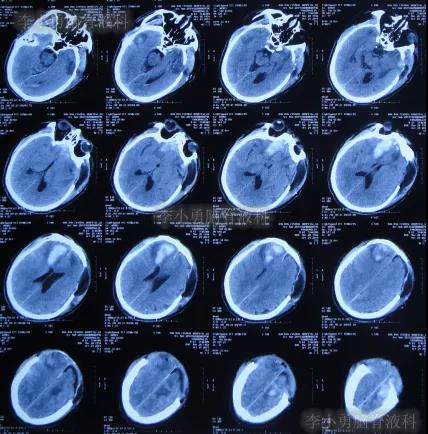

2020年3月18日(颅脑外伤开颅术后149天即颅骨修补术后95天即第2次脑室腹腔分流术后62天,先后经4家医院治疗后仍意识模糊,大小便失禁,脑积水,间断发热近2月)转住入李小勇脑脊液科。入院时:意识模糊,大小便失禁,体重较前明显减轻,体温高38度左右;头部可见引流管走向;右侧肢体活动差些;鼻饲流食(图-30);入院时头颅CT示颅骨修补术后、脑室引流术后仍脑积水,有水肿(图-31)。

图-31:2020年3月18日头颅CT

入院次日拔除了原脑室腹腔分流管+脑室外引流术(图-32)。

图-32:2020年3月19日头颅CT

图-33:2020年3月30日头颅CT

图-34:2020年4月6日头颅CT

入院治疗53天即2020年5月10日,复查头颅CT示脑室缩小(图-38)。

图-38:2020年5月10日头颅CT